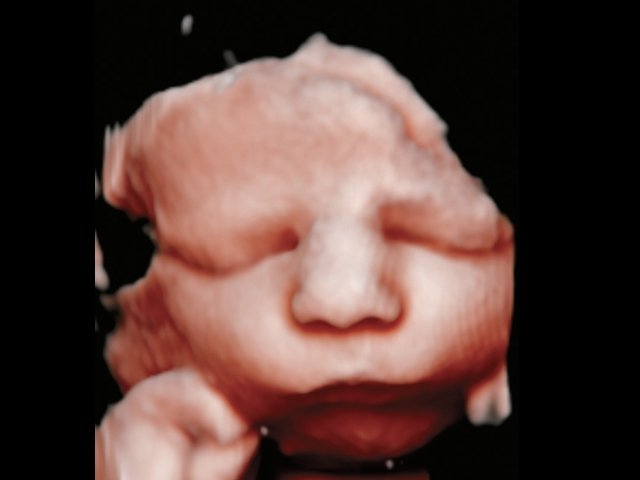

Революцией в пренатальной ультразвуковой диагностике явилось появление объемной эхографии, которая, обладая такими качествами, как неинвазивность, безопасность и возможность многократного применения у одной пациентки, имеет высокую информативность в исследовании анатомии плода и изучении его фенотипа. При применении различных режимов объемной эхографии абсолютно очевидно их преимущество по сравнению с обычным сканированием. Детально можно изучить лицо плода (рис. 1–4) в различные сроки беременности, начиная со сроков первого пренатального скрининга в 11–14 нед, конечности плода, причем не только их наличие и положение (рис. 5, 6), но и состояние и количество пальцев (рис. 7–9) как на руках, так и на ногах. Также можно изучить позвонки плода (рис. 10), состояние твердого нёба (рис. 11, 12), строение наружного уха (ушной раковины) (рис. 13), состояние основных швов черепа и родничков, исключая их преждевременное закрытие при кранисиностозах (рис. 14, 15).

Рис. 1. Нормальное лицо плода, 12 нед беременности.

Рис. 2. Нормальный профиль плода, 21 нед беременности.

Рис. 3. Нормальный профиль плода, 23 нед беременности.

Рис. 4. Нормальный фенотип плода, 34 нед беременности.